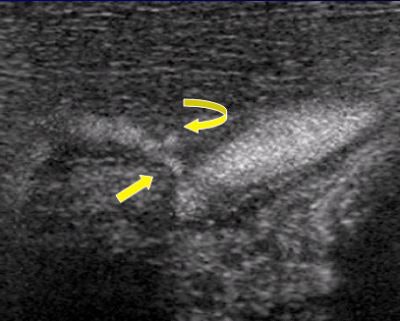

![]() |

| B-flow image provides improved definition of the vessel lumen (straight arrow) and demonstrates ulceration, which was not detected on the Doppler study but confirmed at arteriography. Images courtesy of Dr. John Pellerito. |

B-flow benefits include improved carotid plaque characterization and better demonstration of arterial stenosis and turbulent flow states. B-flow also offers potential in evaluation of high-flow lesions in dialysis fistula and bypass grafts, where color-flow artifacts can obscure the underlying stenosis.

B-flow can demonstrate venous thrombosis, as well as small clots that can be distinguished from flowing blood, Pellerito said. Further research is needed to determine whether B-flow will aid in the diagnosis of diseases of the aorta and deeper branch vessels, he said.